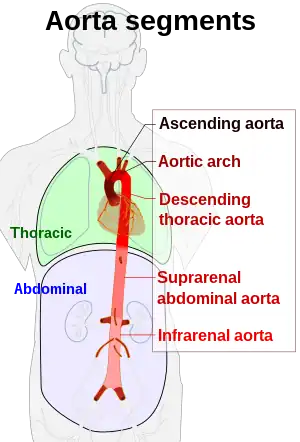

Segments of the aorta, with both suprarenal and infrarenal abdominal aorta | |

In human anatomy, the abdominal aorta is the largest artery in the abdominal cavity. As part of the aorta, it is a direct continuation of the descending aorta (of the thorax).[1]

The abdominal aorta begins at the level of the diaphragm, crossing it via the aortic hiatus, technically behind the diaphragm, at the vertebral level of T12.[1] It travels down the posterior wall of the abdomen, anterior to the vertebral column. It thus follows the curvature of the lumbar vertebrae, that is, convex anteriorly. The peak of this convexity is at the level of the third lumbar vertebra (L3). It runs parallel to the inferior vena cava, which is located just to the right of the abdominal aorta, and becomes smaller in diameter as it gives off branches. This is thought to be due to the large size of its principal branches. At the 11th rib, the diameter is 122mm long and 55mm wide and this is because of the constant pressure.[2] The abdominal aorta is clinically divided into 2 segments:

- The suprarenal abdominal or paravisceral segment, inferior to the diaphragm but superior to the renal arteries.

- The Infrarenal segment, inferior to the renal arteries and superior to the iliac bifurcation.